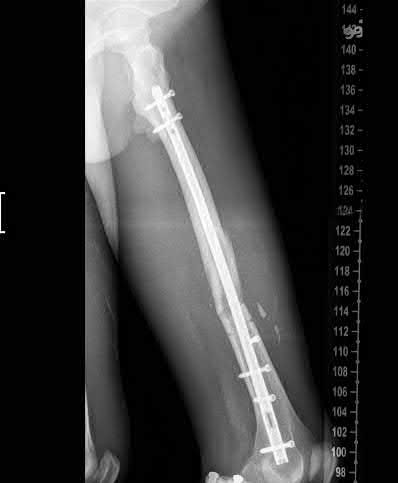

A 30-year-old male with a comminuted tibial shaft fracture complains of escalating leg pain out of proportion to the injury. His blood pressure is 110/80 mmHg. Intracompartmental pressure testing is performed. Which of the following measured thresholds is the most reliable criterion for performing an emergency fasciotomy?

Explanation

The Delta P concept (Diastolic Blood Pressure minus Compartment Pressure < 30 mmHg) is the most reliable and universally accepted threshold for diagnosing acute compartment syndrome. It accounts for the perfusion pressure of the limb, reducing unnecessary fasciotomies in hypotensive patients.